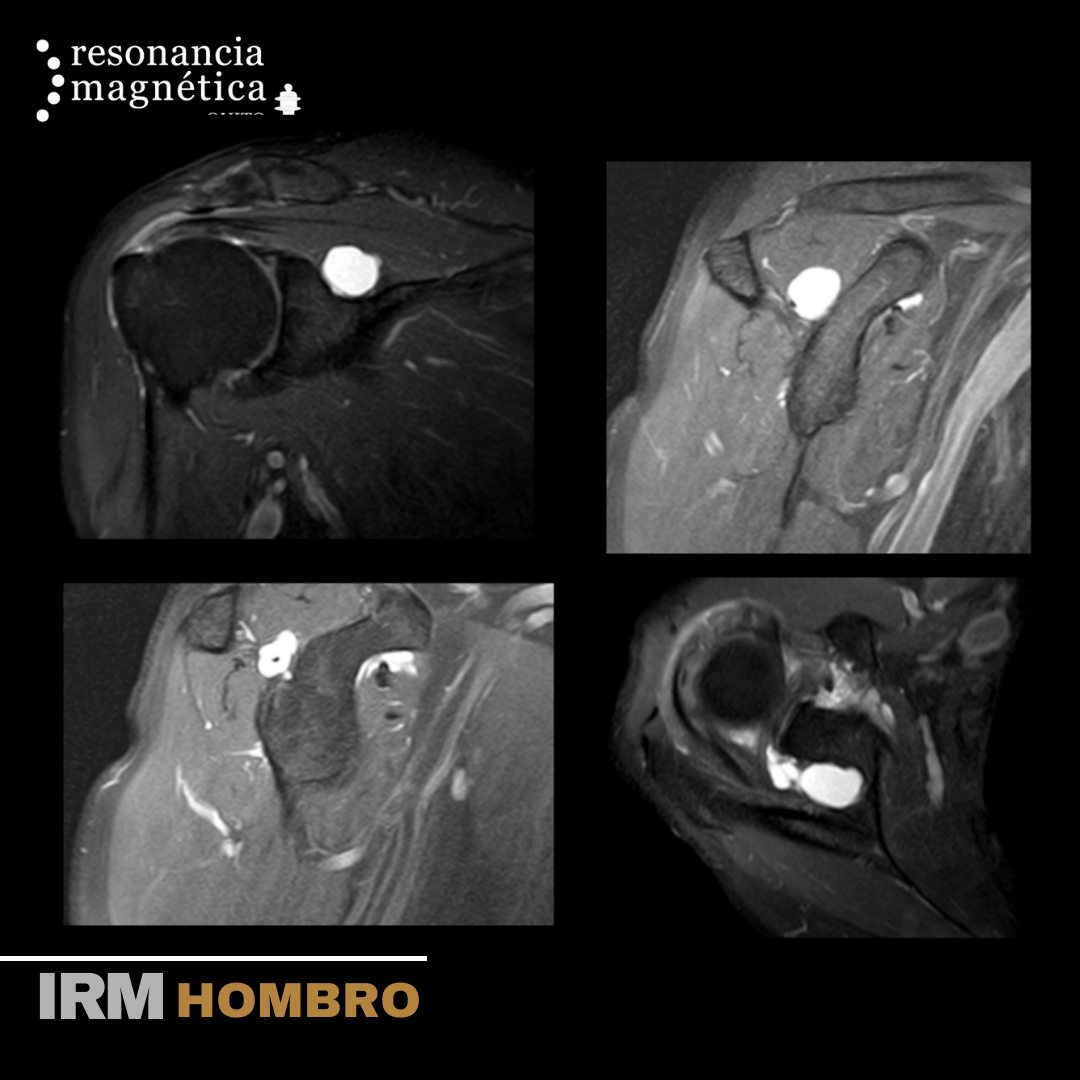

La RMN del hombro provee imágenes detalladas de las estructuras dentro de la articulación del hombro, incluyendo huesos, tendones, músculos y vasos, desde cualquier ángulo. La resonancia magnética nuclear (RMN) es un examen no invasivo que los médicos utilizan para diagnosticar enfermedades.

La subespecialidad osteoarticular permite obtener un diagnóstico preciso y certero en problemas de hombro, mano, cadera, rodilla, tobillo entre otras articulaciones, para que su médico realice el mejor tratamiento clínico o quirúrgico y su recuperación sea rápida y satisfactoria.